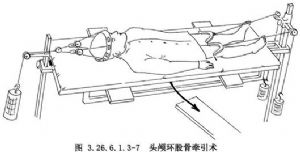

(2)頭顱環股骨牽引裝置(halo-femeral distraction):1959年,首先由Perry和Nickel用頭顱環牽引術(halo distraction)治療頸椎麻痹性疾病,用作外固定。此後發展出現頭顱環股骨牽引術,頭顱環由一個金屬環用螺釘擰緊固定到顱骨上,下端用2根斯氏針固定到股骨上。牽引重量從頭側6kg,雙下肢各3kg開始,逐漸增加到各12kg,牽引2~3周。Letts等報道10例,平均側彎81°,牽引矯正率達57%。此牽引術可引起股骨頭病變,且對脊柱牽引固定不夠,逐漸被頭顱環骨盆牽引術(halo-pelvic distraction)取代(圖3.26.6.1.3-7)。